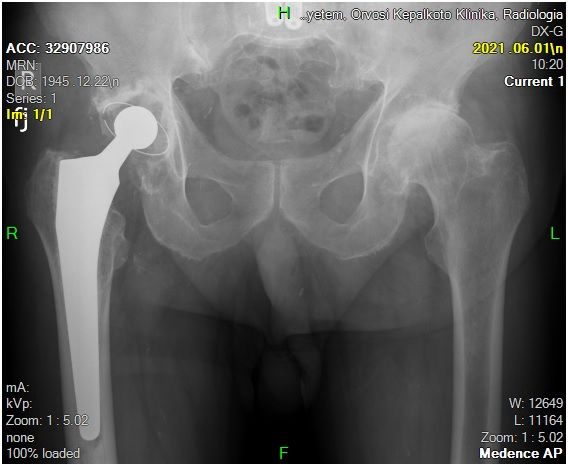

29 éves pályám során közel ezer térdprotézist és több mint kétezer csípőprotézist ültettem be. Az utóbbi években egyre több, nagy műszer igényű, összetett protézis revíziós műtétet végzek.

Fő érdeklődési köröm a biomechanika, műszerfejlesztés, új műtéti technikák kidolgozása és a nagyízületi endoprotetika.